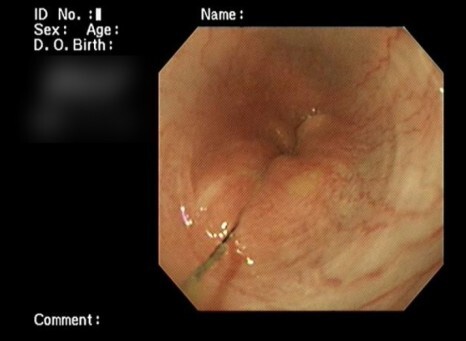

깔끔하게 제거한 선이물입니다.